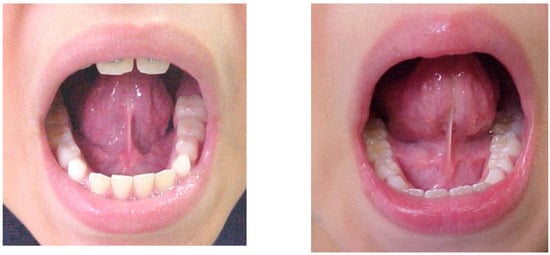

- did not allow adequate movement of the tongue;

- had an insertion in the inferior alveolar ridge or beneath;

- did not allow tongue suction on the palate even if there was an insertion in the midline under the tongue;

- when the tongue was raised the shape of the tip was more square;

- when the tip of the tongue was raised toward the palate only the edges can raise;

- for the tongue to reach the palate the patient needed to almost close the mouth;

- when the tongue is sucked up on the palate the distance between the incisal edges was less than 13mm (Figure 2).